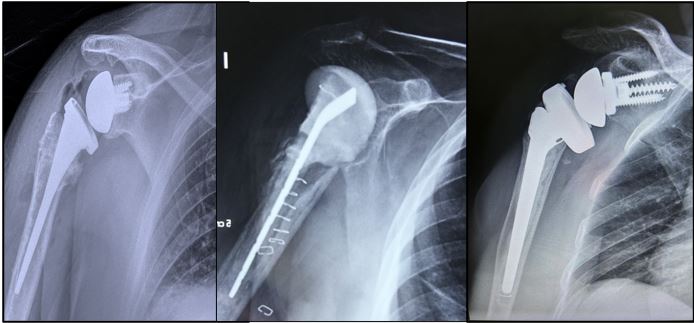

Figura 3. Radiografías, de izquierda a derecha: Rx postoperatorias con prótesis infectada, se puede observar el espaciador Subiton® de hombro prefabricado en posición. Rx postoperatorias con prótesis de revisión